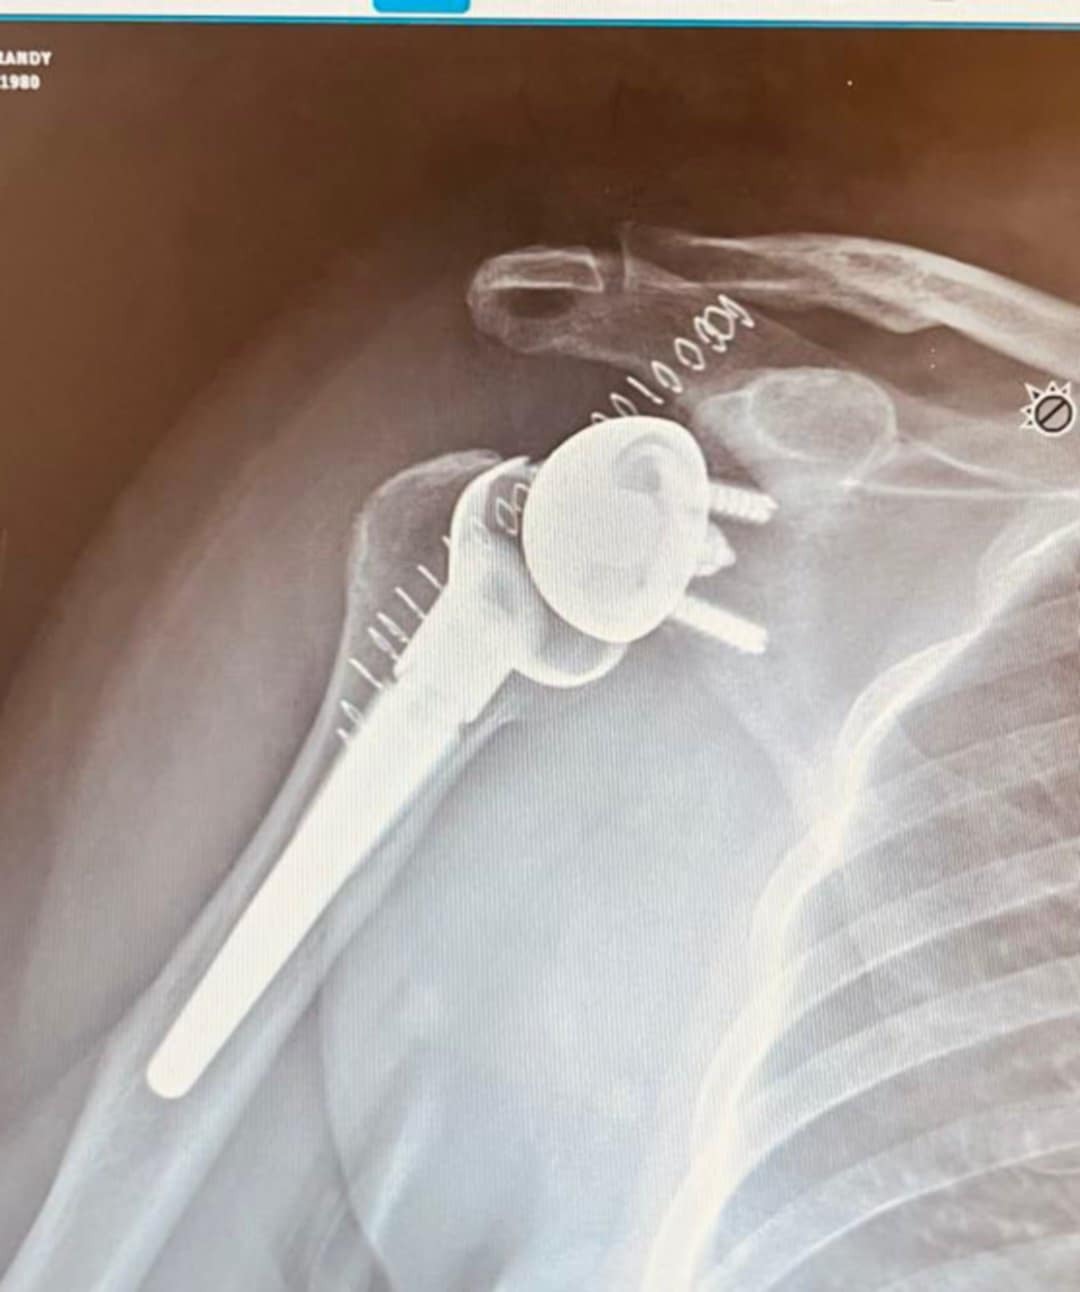

My name is Brandy and last year was a crazy one. First, I started 2025 with a reverse shoulder replacement on my right arm, then 10 months later, I fractured my back bending over stringing a fence. A month after my back fractured, I had the same reverse replacement surgery on my left shoulder. Less than a week after that surgery, my leg started hurting so bad. The doctor said it was just a pulled muscle. About 4 days later, I stepped down a step and my femur snapped in two. While I was in the operation prep room, the surgeon came in and boldly announced I was dying and he wasn't touching my leg as I had cancer and this was it for me. I had an appointment that I was supposed to be at with my hematologist. While letting them know I wasn't going to make my appointment, I explained why and it turns out my hematologist was also an oncologist. He called the surgeon and explained my cancer to him. Turns out I have multiple myeloma, blood bone marrow, plasma cancer, and that's the reason for all my breaks. He told the surgeon that it couldn't spread anymore than it had and I couldn't be left laying there in pain. Two hours later, I was in surgery. Now, when I finally got to talk to the oncologist/hematologist, he explained that multiple myeloma is a 3-stage cancer and I was in stage 3 with a year to live without treatment. It took me a while to swallow that pill. Then I had to tell my kids, 3 girls aged 21, 20, and 9, and my son (also 9, boy-girl twins) that I had cancer, which meant I didn't know how long I had. It could be a year, it could be 5 with treatment.